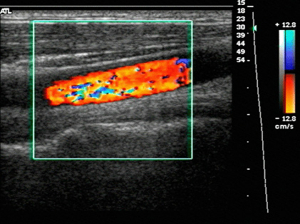

- 일반 초음파의 원리에 도플러 효과를 적용한 검사로, 움직이는 혈액의 속도와 방향을 실시간으로 측정할 수 있습니다.

- 혈관 내 혈류의 특성을 분석해 혈류가 정상적으로 흐르는지, 역류나 협착이 있는지 평가할 수 있습니다.

- 혈관의 기능적 상태를 파악하는 데 중요한 역할을 하며, 하지정맥류, 동맥 협착, 혈전 등 혈관 질환 진단에 쓰입니다.

도플러 초음파는 혈관 내 혈액의 흐름과 속도, 방향 등 혈류역학적 정보를 측정하는 검사입니다.